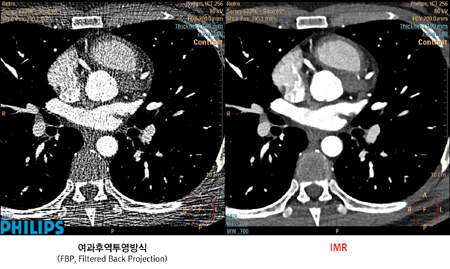

필립스 IMR은 저대조도 분해성능을 개선시켜 매우 적은 선량으로도 노이즈가없는 고품질의 영상을 구현한다. IMR은 표준 재구성 기술에 비해 방사선량을 60~80% 감소시키는 동시에, 저대조도 분해성능을 43~80% 개선시켜 노이즈를 70~83%까지 줄인다.